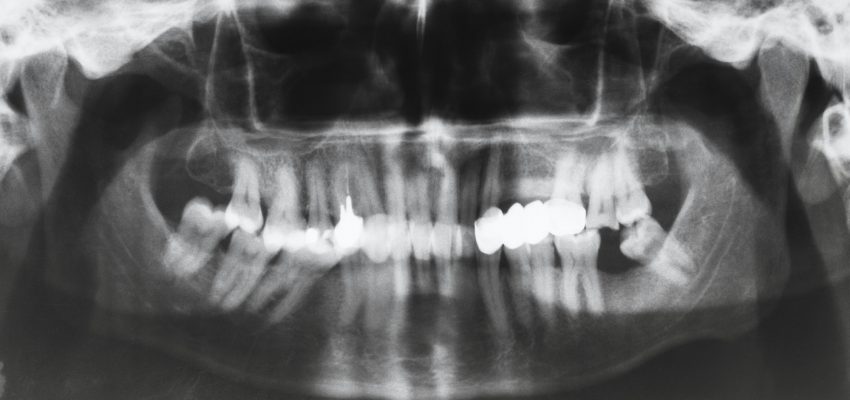

זהו צילום שנשלחים אליו מטופלים על ידי רופאי השיניים שלהם כדי לקבל תמונה כוללת על מצב השיניים בכלל בתוך הפה המטופל, צילום פנורמי שיניים נעשה בהרבה מהמקרים במכונים עם מכשיר המותאם לביצועי צילומים שכאלה, ניתן בעזרתם גם לבצע צילום נשך, צילום סטטוס לפה זאת בנוסף לצילום שיניים פנורמי שהתוצאה שלו היא תצלום כוללני ומדויק של חלל הפה שאפילו ניתן לראות את חלל הסינוסים.

צילום פנורמי שיניים משמש לרוב כבסיס לקביעת תכנית הטיפולים של השיניים במידה כמובן שגם יש צורך בטיפול מקיף שנתבקש לפעמים מראש על ידי הרופא השולח או המטפל בחולה, לדוגמא האם יש צורך בעקירה פשוטה או עקירה כירורגית לשן מסוימת כשאין החלטה חד משמעית איך לטפל בה, האם יש צורך בטיפולי שרש כאלה ואחרים או לראות לפעמים בעיות במבנה הלסת שמצריכים טיפולים בלסת ולא בשיניים, צילום שיניים פנורמי אשר גם נותן מבט מקיף על חלל הסינוסים ויכול גם להראות על דלקות או גידולים בחללים אלו.

רוב מכוני הצילום המוכרים והרציניים שביניהם מתחייבים לצילום שיניים פנורמי שנעשה במכונם, בעת מהלך צילום פנורמי לשיניים המכונות המבצעות את הצילום מבצעות סריקה מעגלית על חלל הפה ומבנה הלסת, רצף התמונות הנאסף במהלך זה יוצר תמונה אחת פנורמית על האזור המצולם, רמת הקרינה כיום במכשירים אלו היא יחסית נמוכה לעומת העבר ועדיין יש צורך בלבישת חליפת עופר עליונית כדי למנוע סכנת קרינה, כיום גם המכונות דיגיטליות ורמת הדיוק של עבודתן הוא אבסולוטי כמעט.